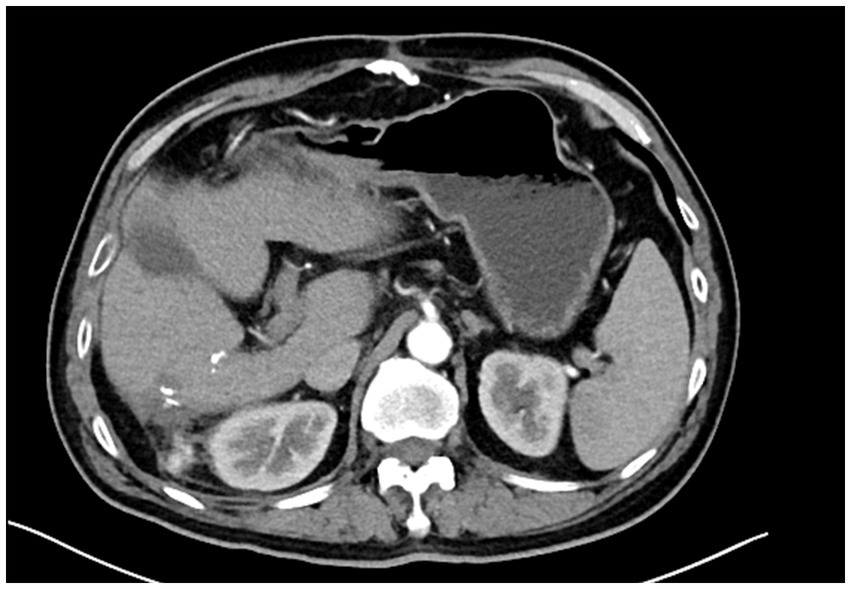

Primary hepatic malignant mesothelioma (PHMM) is an uncommon and aggressive neoplasm with vague clinical and radiological features, posing challenges for preoperative diagnosis. In our case, a lobulated hepatic mass demonstrated a serpiginous peripheral enhancement pattern on contrast-enhanced CT and MRI. This uncommon imaging manifestation has been sporadically documented in previous reports. By consolidating these findings, our report emphasizes serpiginous peripheral enhancement as a potential diagnostic clue for PHMM. Recognition of this pattern may aid earlier detection, improve differential diagnosis, and guide timely surgical decision-making in affected patients.